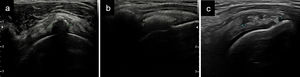

Calcificación tipo I o dura. Imágenes hiperecogénicas con sombra acústica posterior muy definida que borra la cortical humeral (fig. 2a). Corresponden con la fase de calcificación. No suelen ser muy sintomáticas.

Figura 2.Tipos de calcificaciones en los tendones del MR según su densidad: a) Calcificación tipo I, señalada entre 2 cruces, se observa una sombra acústica posterior que borra completamente la cortical humeral; b) Tipo II (entre cruces), menor ecogenicidad con sombra acústica que borra de manera parcial la cortical; c) Tipo III (entre cruces), grumosa sin sombra acústica posterior.

Calcificación tipo II o intermedia. Más ovaladas y menos definidas con una sombra acústica que borra de manera parcial las estructuras (fig. 2b). Corresponden a estadíos iniciales de la fase reabsortiva. Suelen ser más sintomáticas que las tipo I.

Calcificación tipo III o blanda. Aspecto grumoso, semilíquidas, peor definidas y sin sombra acústica (fig. 2c). Corresponden con la fase reabsortiva y son muy sintomáticas10.